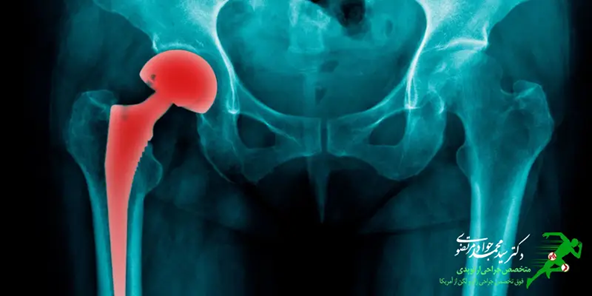

تجویز داروها به منظور کاهش درد بیمار بهتر است تحت نظر متخصص ارتوپدی انجام گیرد. از رایج ترین روش درمان این بیماری جراحی می باشد. جراحی تعویض مفصل ران شامل جابجایی قسمت آسیب دیده استخوان ران و قرار دادن قسمت مفصل مصنوعی در محل مورد نظر است. در صورتی که تحت جراحی قرار گرفته باشید، انجام فیزیوتراپی به منظور افزایش سرعت بهبود درمان توصیه می شود.